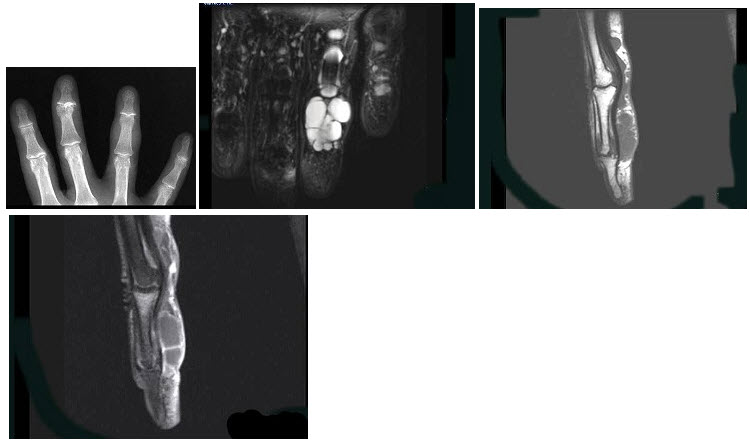

168、单项选择题

男,3岁,腕部变形,胸廓畸形,应诊断为()

A.坏血病

B.佝偻病

C.粘多糖病

D.克汀病

E.脂质沉积病